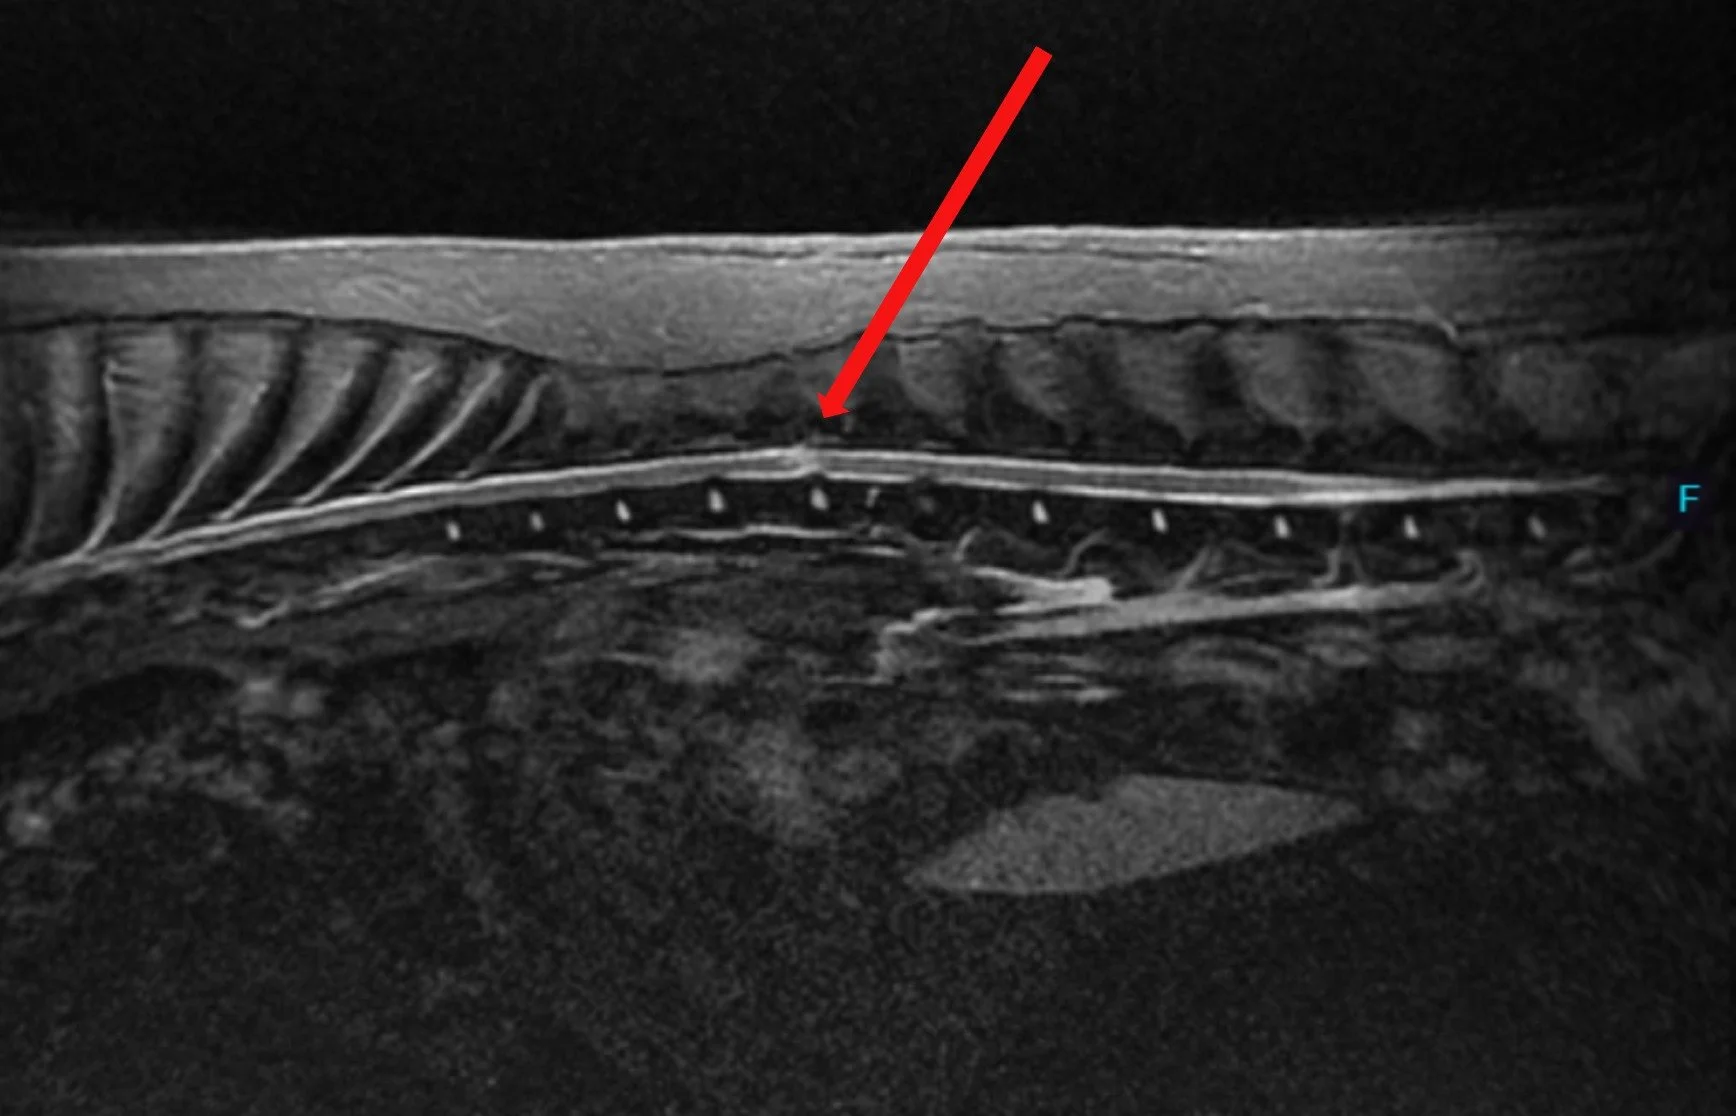

Sagittal view of Juno’s spine - MRI STIR sequence. The red arrow points toward the lesion in the middle of the spinal cord which is bright in this sequence and lies right above the T13-L1 disk space.

Sagittal view of patient’s spine - MRI STIR sequence. The red arrow points toward the lesion in the middle of the spinal cord which is bright in this sequence and lies right above the T13-L1 disk space.